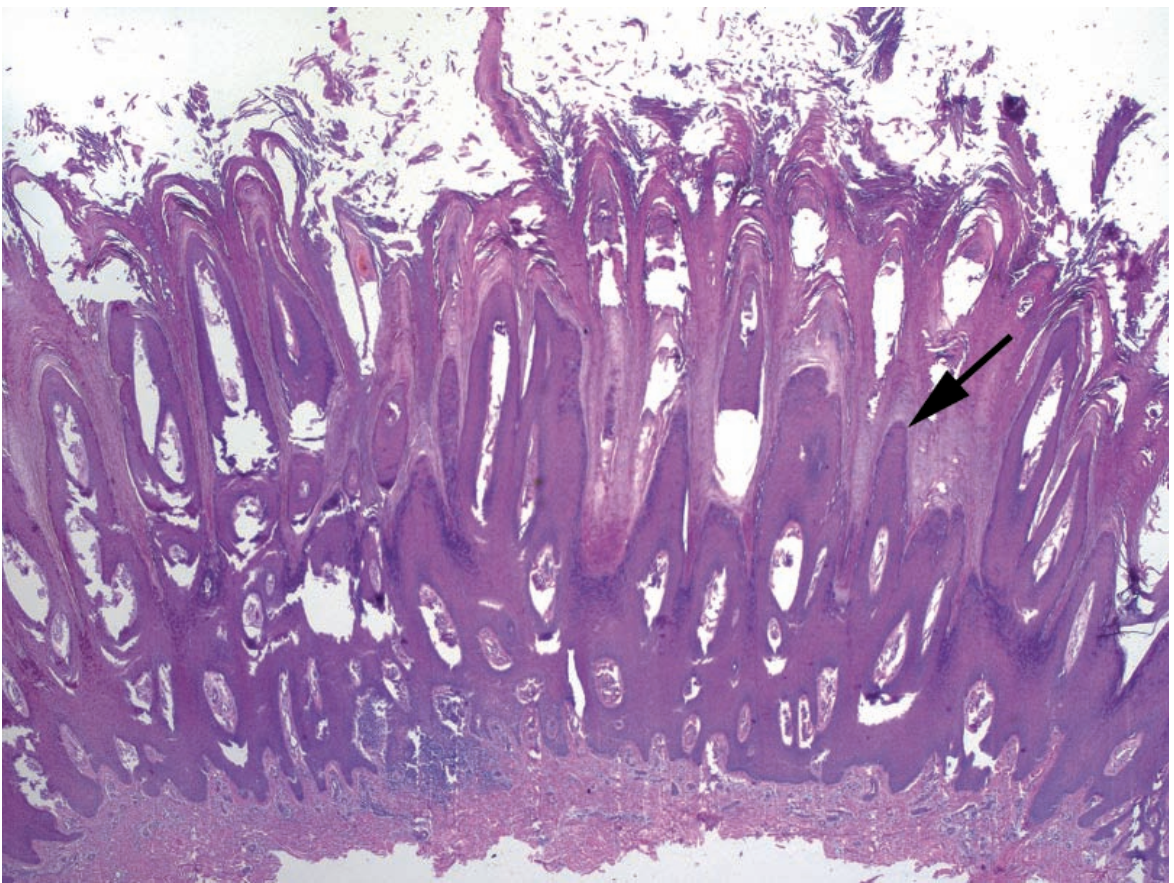

Q

A

Verrucous wart

Arrow: Exophytic spires with hyperkeratosis & parakeratosis